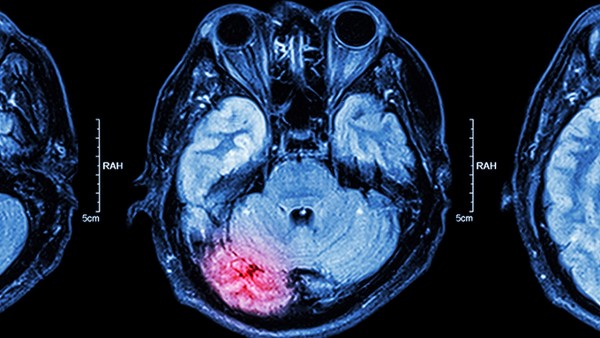

2、脑梗塞的前兆

1、头晕、头痛突然加重

或由间断性头痛变为持续性剧烈头痛。一般认为头痛、头晕多为缺血性脑梗塞的先兆,而剧烈头痛伴恶心、呕吐则多为出血性脑梗塞的先兆。